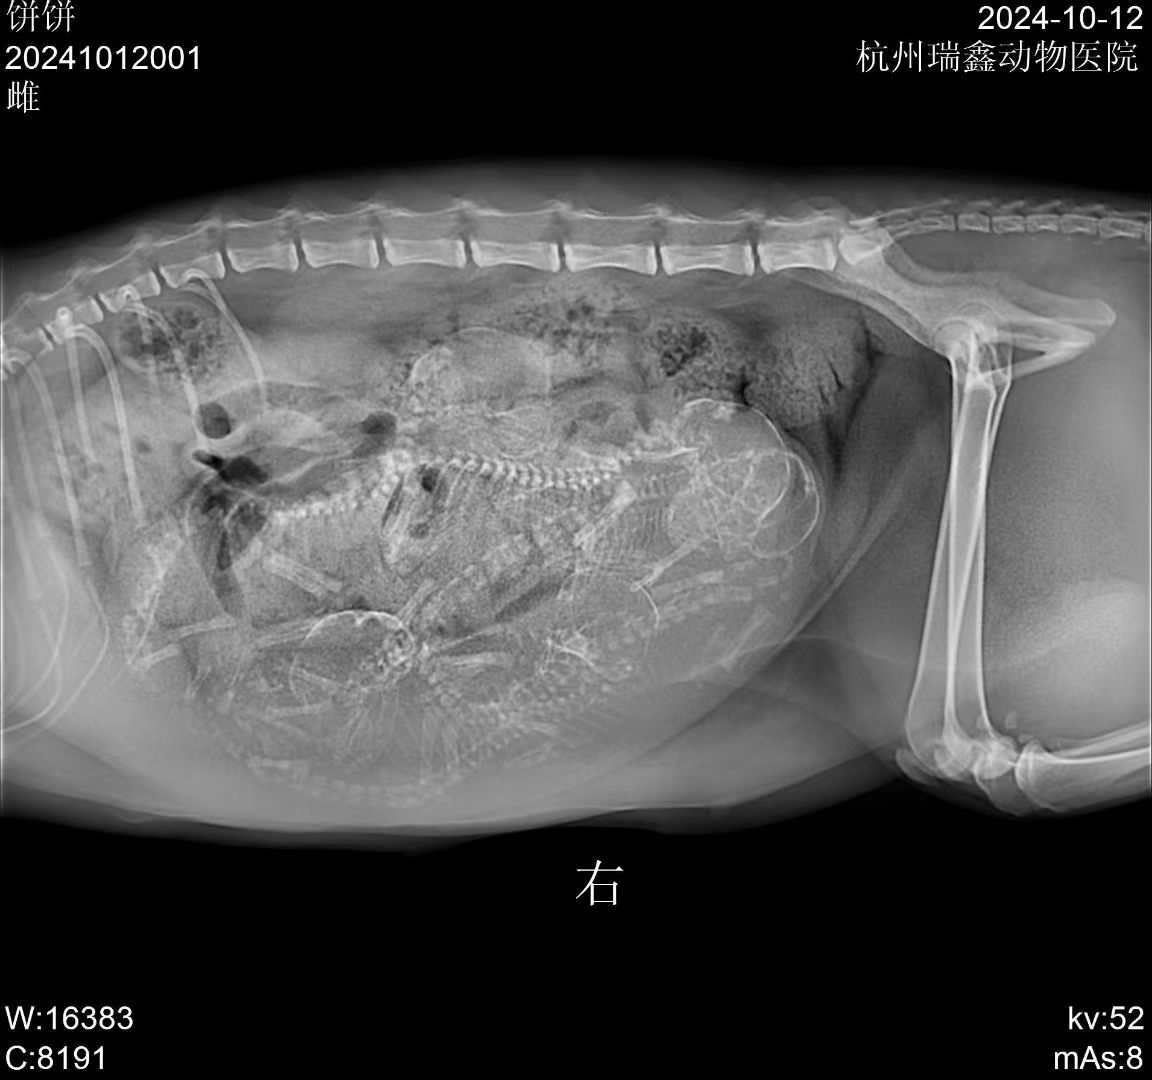

前几天的一个咨询 💬

铲屎官说猫咪一岁多,刚养了两个月

症状描述:​腹部隆起,呼吸急促,看了视频有点腹式呼吸,建议抓紧拍个片子🔍

——原来这是怀了啊,喜提小猪咪五只 😄